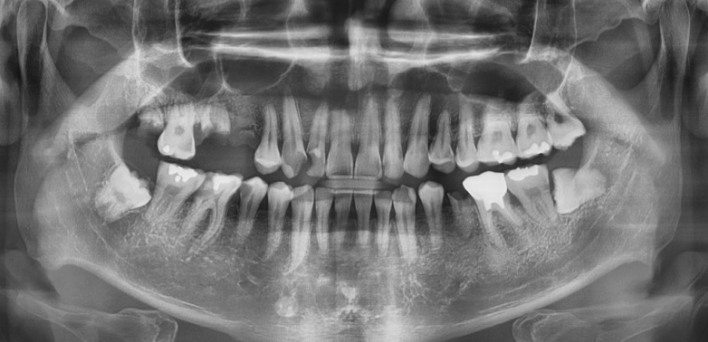

정확한 안모 맞춤형 분석

더서울치과의원은 개인의 얼굴과 가장 잘 어울리는 치아의 형태와 색상을 분석하고,

분석한 데이터를 기반으로 맞춤형 보철을 진행합니다.

더서울치과의원은 정확한 안모 분석을 통한 프로파일 예측 치료로 심미성은 물론 치아 본연의 기능 회복까지 가능하도록

안면 근육과 기능, 치아 형태, 비율, 크기, 교합, 색감 등 전반적인 비율을 맞추어 본인에게 잘 맞는 치아의 형태로 복원합니다.